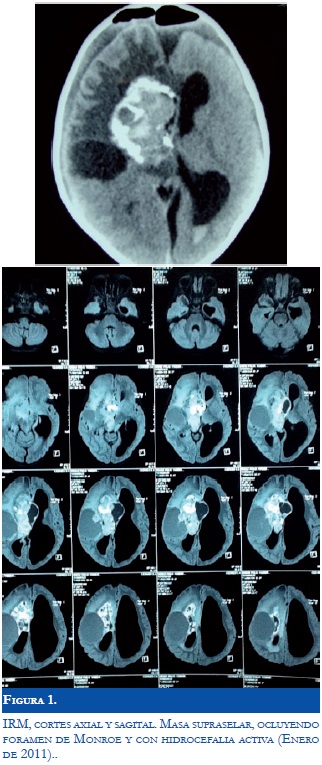

Paciente de 4 años, 10 meses quien es llevado a consulta externa por su madre por presentar limitación en la movilización del hemicuerpo izquierdo de comienzo súbito. No antecedentes de importancia. Al examen físico la única alteración evidente fue hemiparesia izquierda. Se plantea como hipótesis diagnostica inicial lesión supratentorial derecha por lo que deciden hospitalizar el paciente para realizar estudios complementarios. Realizan TAC cráneo, el cual reporta lesión intraxial compleja, de gran tamaño con componente quístico y sólido con calcificaciones, originado desde la cisterna supraselar con dilatación del sistema ventricular izquierdo. Ante estos hallazgos, deciden realizan resonancia magnética nuclear, en la cual describen lesión supraselar de 5 cms que afecta tálamo, quiasma óptico, cisterna supraselar, cisterna de la lámina terminalis y comprime foramen de Monroe, con gran porción solida calcificada y porción quística frontoparietal derecha (Figura 1). Con estos resultados, es evaluado por neurocirugía quien decide realizar resección quirúrgica total, la cual debe ser suspendida por sangrado abundante durante el procedimiento y por el gran tamaño de la lesión, colocan sistema de derivación ventrículo peritoneal y remiten al paciente a nuestra institucion para continuar manejo en unidad de cuidados intensivos Pediatricos, Neuropediatria y Oncología Pediatrica. El resultado de la patología de la lesión extraída reporta neoplasia compuesta por células grandes, estrechamente agrupadas con citoplasma poligonal similares a células ganglionares con núcleo grande, redondo vesicular, con nucléolo prominente y citoplasma eosinófilo. Hay otras células elongadas dispuestas en medio de una matriz fibrilar; el estroma en áreas es de aspecto fibroso y se observan vasos elongados con luces colapsadas. Hacia la periferia hay células multinucleadas y calcificaciones dispersas. Proteína fibrilar acida positiva en astrocitos dispersos. Sinaptofisina positiva en algunas células gigantes similares a células ganglionares. Cd34 positiva en la pared de los vasos. Ki-67 positivo en 1.2%. Se confirma la impresión diagnóstica previa de Astrocitoma Subependimario de Células Gigantes ( SEGA). Durante la evolución el paciente presenta convulsiones y en monitoreo video-EEG se confirma foco epileptiforme frontal derecho iniciándose manejo antiepiléptico con carbamazepina y posteriormente se adiciona topiramato. Se realizan exámenes complementarios (ecografía abdomen total, ecocardiograma y evaluación por oftalmología) en busca de otros criterios diagnósticos de Complejo de Esclerosis Tuberosa, pero no se encuentran otras alteraciones asociadas.